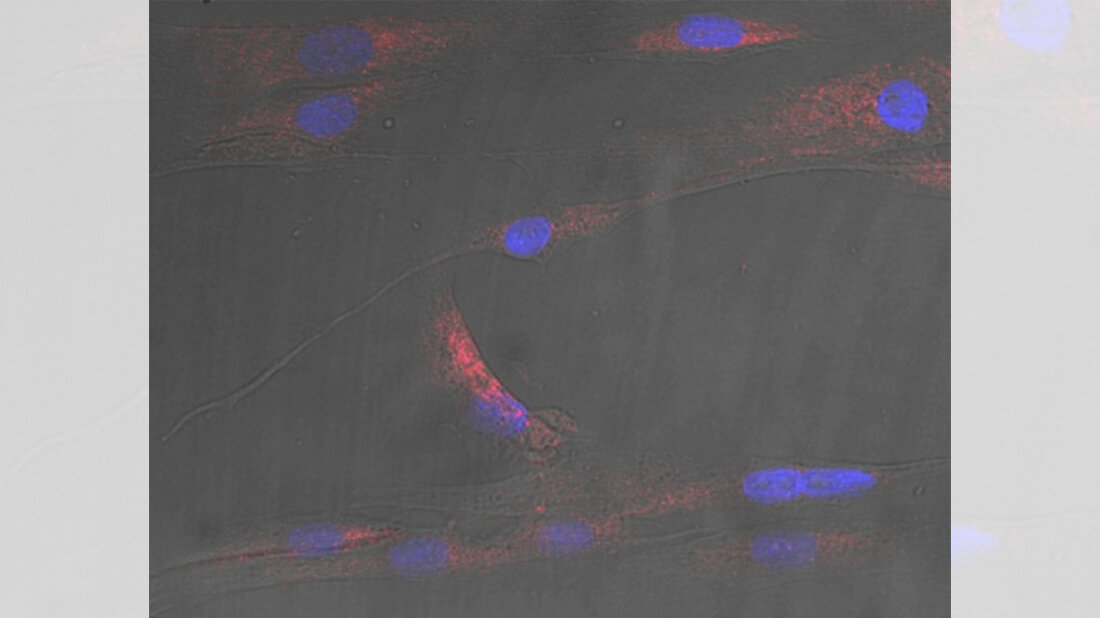

Das Forschungsteam replizierte im Labor die bei Menschen mit Stoffwechselkrankheiten beobachteten Blutfettwerte, indem es Skelettmuskelzellen einer Fettsäure namens Palmitinsäure aussetzte. Die Zellen begannen, die Palmitinsäure in Ceramid umzusetzen und als Ceramid-Signal zu übertragen. Wurden diese Zellen mit anderen gemischt, die zuvor nicht mit Fetten in Berührung gekommen waren, stellten die Forscher fest: Die Zellen kommunizierten miteinander und transportierten das Ceramid-Signal in Paketen, sogenannten extrazellulären Vesikeln.